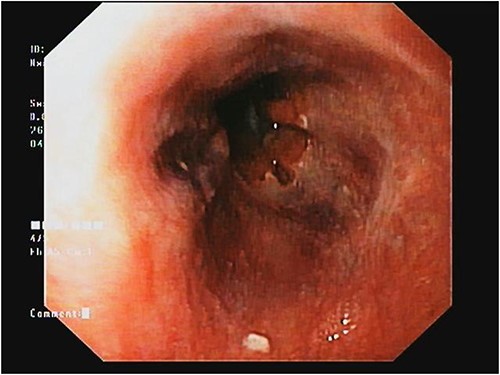

The patient was monitored for vital signs, pain, and fluid balance during the immediate post-operative period. She had an uneventful recovery and was discharged on the third day after surgery (Fig. 4).